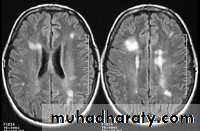

-MRI is more sensitive than CT in the demonstration of MS plaques.

- the most characteristic appearance is that of peri ventricular nodular Hyper intense lesions on T2 weighted images.

-the plaques are also well seen at the gray- white matter interfaces.

-contrast enhancement after giving gadolinium occurs in the acute phase indicating activity & in the chronic phase doesn't enhance.

SAGITAL FLUID ATTENUATION INVERSION RECOVERY SEQUENCE: OVOID PLAQUES ( HIGH SIGNAL INTENSITY) , WHICH ARE PERPENDICULAR TO LATERAL VENTRICLE.